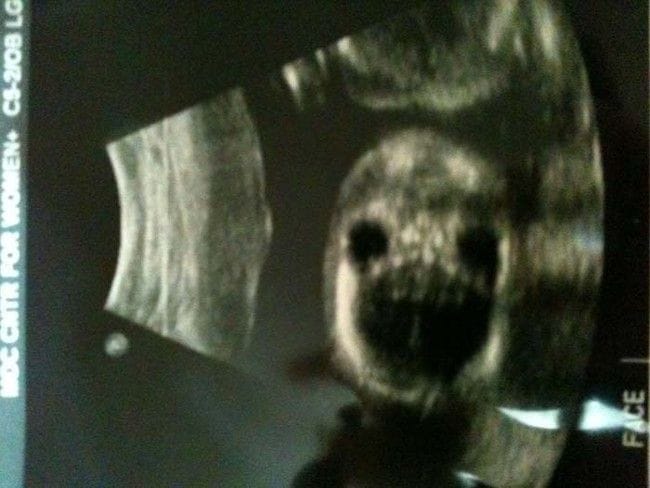

gif_animation 以前「出生前検査をしなかった妊婦から生まれた赤ちゃん」を紹介しましたが、今度はアゼルバイジャンにて、出産を安く済ませようと個人の病院に通い、詳細な検査をしなかったという妊婦から生まれた赤ちゃん。医師によると体自体は極めて健康であるため、少なくとも生存は出来るであろうとの事。(※ TOP画はイメージ)